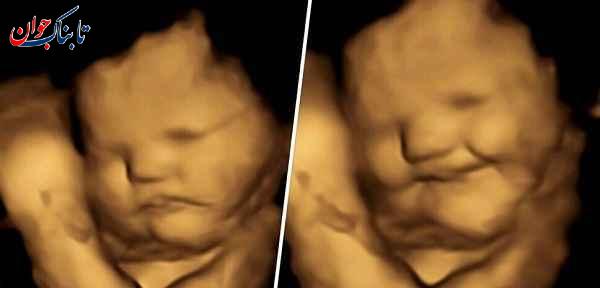

همشهری آنلاین نوشت: تصاویر سونوگرافی جنینها نشان میدهد آنها در رحم مادرشان از برخی غذاها لذت میبرند و برخی را دوست ندارند، نتایج این مطالعه روند از شیر گرفتن و تغذیه سالم نوزادان را دچار تحول میکند. محققان شواهد خوبی مبنی بر اینکه جنین انسان به طعم و بوی خوراکیها در رحم واکنش نشان میدهد پیدا کردهاند.

در این مطالعه، محققان به ۱۰۰ زن باردار یک کپسول حاوی تقریباً ۴۰۰ میلیگرم هویج و یا پودر کلم پیچ دادند و از آنان خواستند تا حدود یک ساعت قبل از سونوگرافی ۴ بعدی، هیچ غذا یا نوشیدنی طعمدار دیگری مصرف نکنند.

۲۰ دقیقه پس از اینکه مادران کپسول هویج یا کلم پیچ را خوردند، محققان آزمایشگاه تحقیقات جنین و نوزاد دانشگاه دورهام در بریتانیا کار تصویربرداری را شروع کردند و در کمال تعجب با واکنش و میمیکهایی دیدنی از صورت جنینها روبرو شدند.

جنینهایی که مادرانشان کپسول هویج خورده بودند، واکنشهای خنده بیشتری نشان دادند، در حالی که آنهایی که طعم کلم پیچ را چشیدند، واکنشهایی شبیه به گریه نشان دادند.

بیزا اوستون، محقق ارشد، محقق ارشد در آزمایشگاه تحقیقات جنین و نوزادان در دورهام، گفت: دیدن واکنش نوزادان متولد نشده به طعم کلم پیچ یا هویج در طول اسکن و به اشتراک گذاشتن آن لحظات با والدینشان واقعا شگفت انگیز بود. واکنشهای صورت این بچههای بانمک با گروه کنترلی که در معرض هیچ کدام از طعمها قرار نگرفتند مقایسه شد.